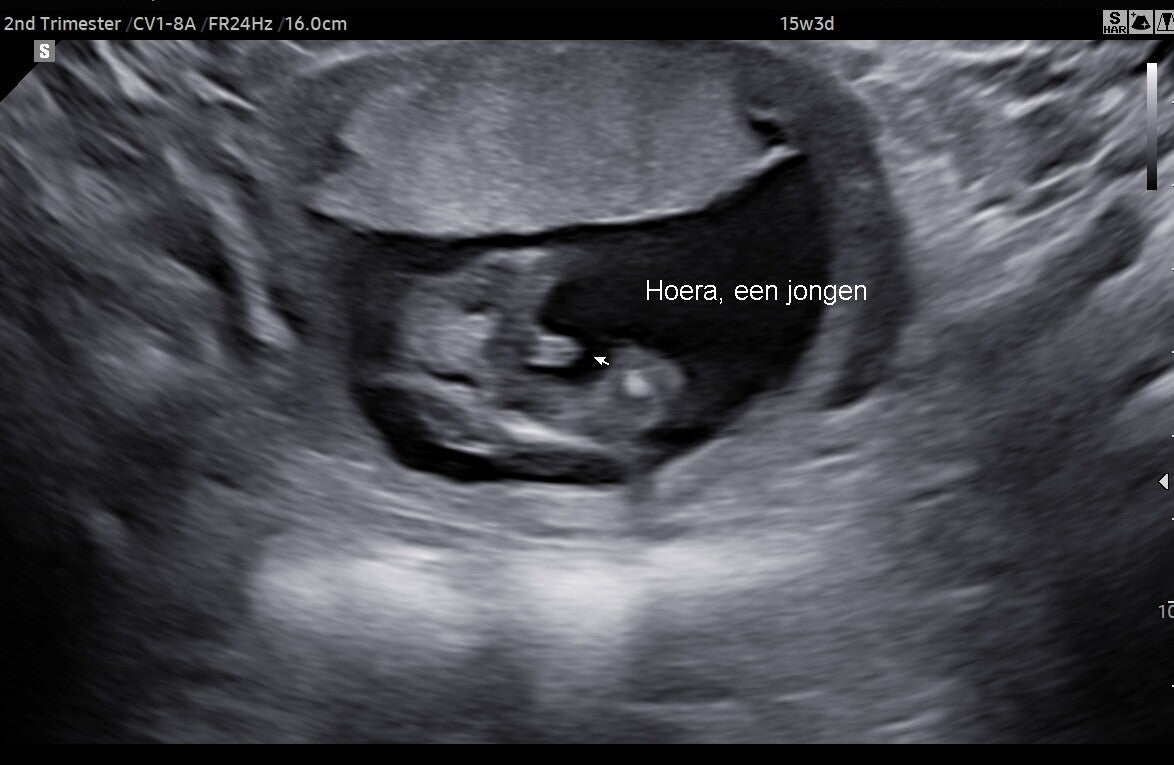

Veel toekomstige ouders zijn toch wel nieuwsgierig naar het geslacht van hun kindje. Word het een jongetje of toch een meisje? Vanaf de 13 weken is het geslacht voldoende ontwikkeld om het te kunnen laten zien. Daarom bieden wij vanaf 13 weken een echo met geslachtsbepaling aan.

• Checken van het geslacht

• Foto van het geslacht